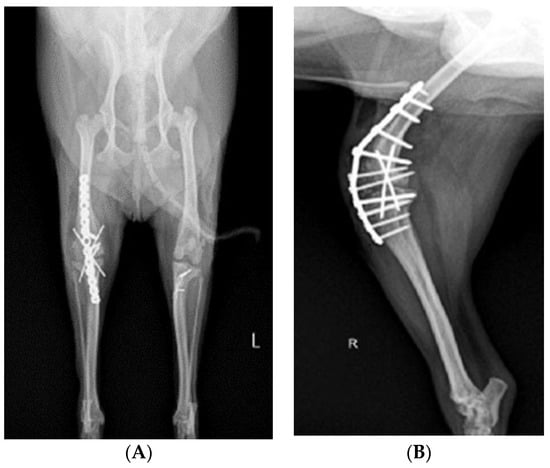

Before surgery, antibiotic and anti-inflammatory drugs were applied for about a month to relieve pain, edema, and arthritis; then, the surgery was performed. For treatment, amoxicillin/clavulanic acid (12.5 mg/kg, Amocla, KUHNIL corp., Seoul, Republic of Korea), carprofen (2.2 mg/kg, RIMADYL, Zoetis Inc., Parsippany-Troy Hills, NJ, USA), tramadol (2 mg/kg, Tridol cap. Yuhan Corp, Seoul, Republic of Korea), and famotidine (0.5 mg/kg, Famotidine, Hanmi Pharm, Seoul, Republic of Korea) were prescribed BID for 4 weeks. After one month, radiographic findings confirmed that inflammation and edema in both stifle joints were reduced (Figure 2). The owner was informed that stifle joint arthrodesis was to be performed on the right hind limb due to severe osteoarthritis, loss of the patella, and rupturing of the cranial cruciate ligament and that MPL correction was to be performed on the left leg. Accordingly, the consent of the guardian was obtained.

Figure 2.

Preoperative craniocaudal (A) and mediolateral (B,C) radiographs of the right and left stifle joints. The prescribed anti-inflammatory drugs reduced pain, lowered fever, and decreased inflammation (swelling and damage) after about a month. Arrows in images show areas with significantly reduced inflammation and edema compared to a month prior.